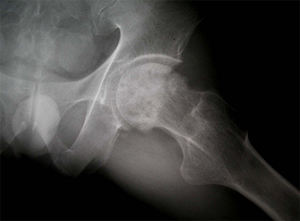

• 수술 전 고관절 X-선 수술 전 고관절 X-선 사진

• 고관절 치환술 후 X-선 고관절 치환술 후 X-선 사진